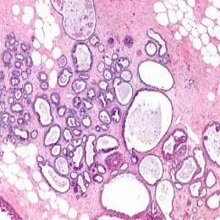

| Цироза јетре је хронична болест код које оштећење ћелија јетре изазива инфламацију, некрозу и активацију звездастих ћелија што доводи до инсуфицијенције јетре и / или малигног тумора. |